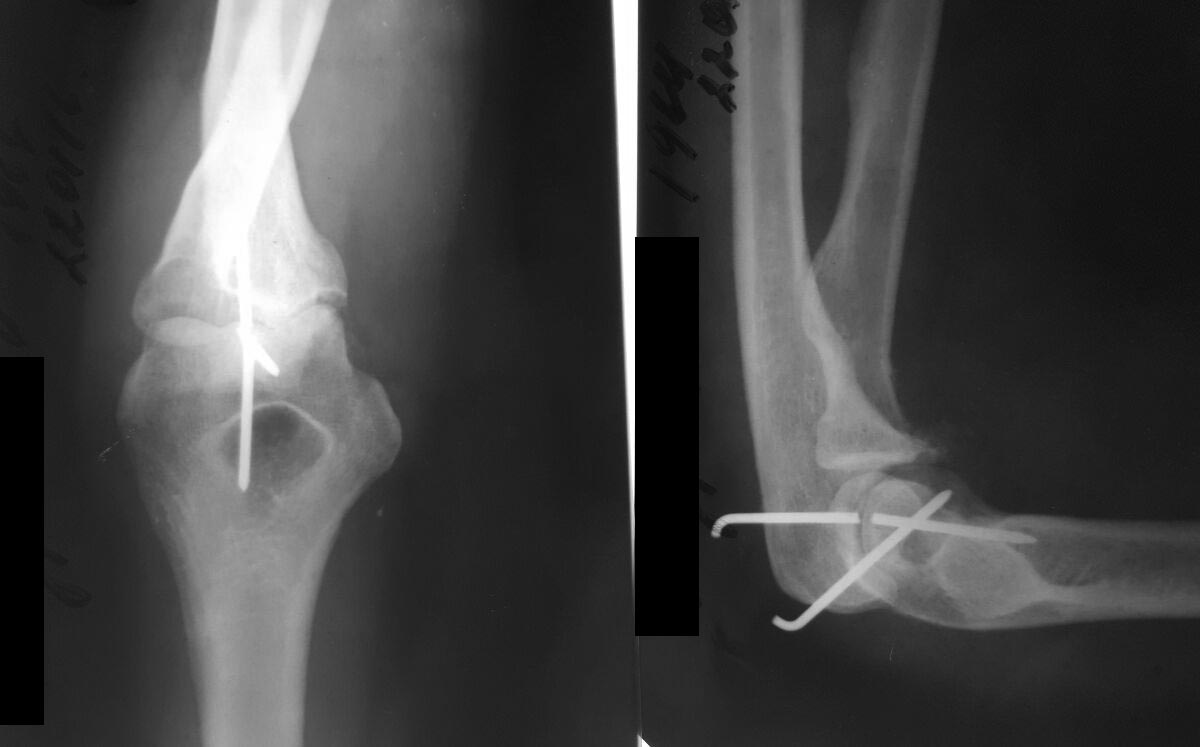

Доброго времени суток, уважаемые коллеги. Женщина 47лет. Три недели

назад произведено открытое вправление по поводу застарелого вывиха

предплечья.

Фиксировано двумя спицами. Сейчас обратилась для удаления спиц и

проведения ЛФК.На рентген контроле выявлен перелом спицы. Посоветуйте,

как ее теперь удалить.